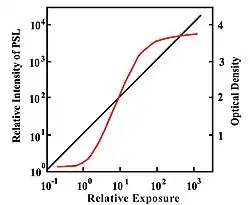

A second parameter to be derived from the transfer characteristic is the dynamic range, which expresses the range of input signals over which the image receptor is sensitive. In the case of CR, its about four orders of magnitude - see Figure 6.3, which shows its transfer characteristic in comparison to the traditional film/screen technology. The result is that under-exposure and over-exposure of regions traditionally seen radiographs are much less of an issue in clinical imaging. This feature of CR is illustrated by the radiographs in Figure 6.4.